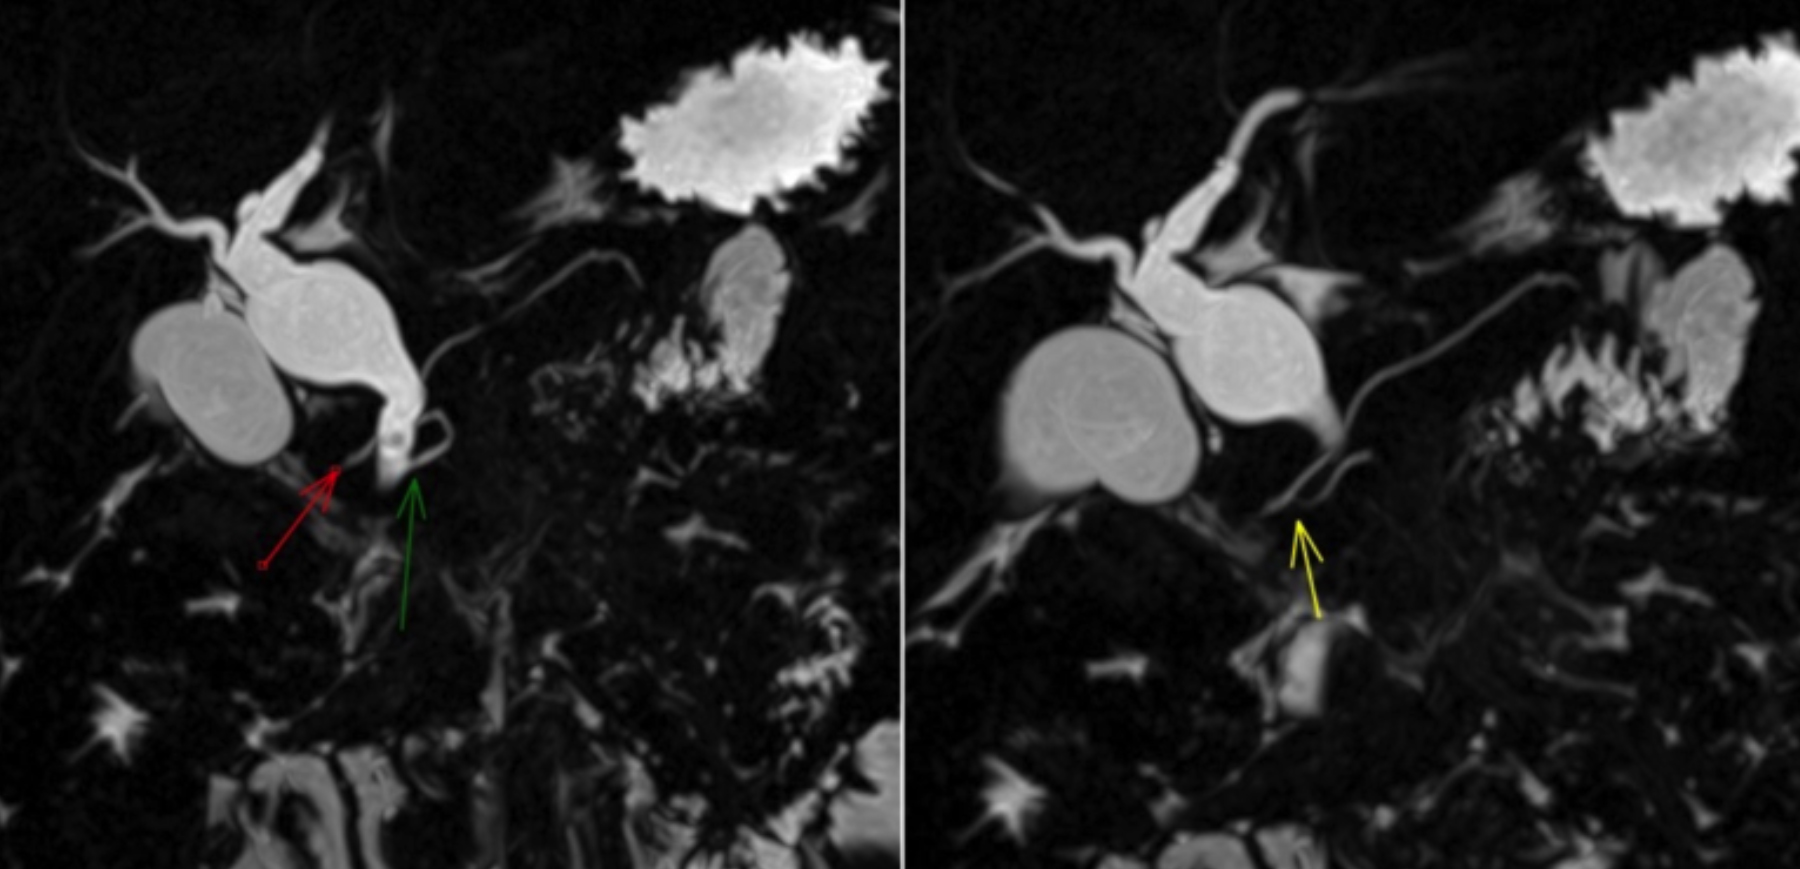

The patient was shifted to the floor, and MRCP was planned. The MRCP showed a dilated, ballooned-out proximal CBD with a calibre reaching up to 15 mm, along with multiple variable-sized internal filling defects likely representing type I choledochal cysts with choledocholithiasis (Figure 1, 2). Mild intra- and extrahepatic biliary dilatation was noted. The pancreatic duct exhibited variant anatomy, with the main pancreatic duct draining via the minor papilla and a small ventral duct draining into the CBD via the minor papilla. There was a rudimentary communication between the dorsal and ventral pancreatic ducts, suggesting pancreatic divisum (incomplete / type III, Figure 3).

Figure 2: 3D reconstructed image of MRCP showing dilatation and ballooning of proximal CBD suggesting choledochal cyst represented by the red arrow. Few filling defects in distal CBD suggest choledocholi- thiasis.

Figure 3: 3D reconstructed image of MRCP showing pancreatic divisum with major / dorsal pancreatic duct opening via minor papilla (red arrow) and ventral pancreatic duct opening with CBD via major papiila (green arrow). Rudimentary communication of dorsal and ventral pancreatic duct (yellow arrow) suggest incomplete Type III pancreatic divisum.